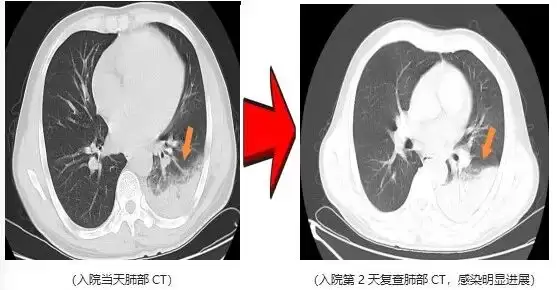

近日,一名爱鸟人士因持续高热、剧烈咳嗽,紧急就诊并收治于杭州萧山区中医院呼吸内科。入院后予以常规抗感染治疗2天,患者高热症状仍反复,最高体温升至40.5℃,伴干咳气促、夜间难以入眠,病情进展后更出现咯血及呼吸衰竭表现。

鉴于患者病情呈重症化趋势,在排除急性肺栓塞等支气管镜检查禁忌证后,医院呼吸内科团队第一时间为患者完善支气管镜检查,同步采集肺泡灌洗液行病原学宏基因组测序,最终锁定致病“元凶”——鹦鹉热衣原体该病原体正是源于患者饲养的宠物鹦鹉。

明确病因后,医护团队予针对性特效药物干预。仅2天后,患者体温恢复正常,干咳气促、咯血及呼吸衰竭等症状均显著缓解,后续顺利康复出院。